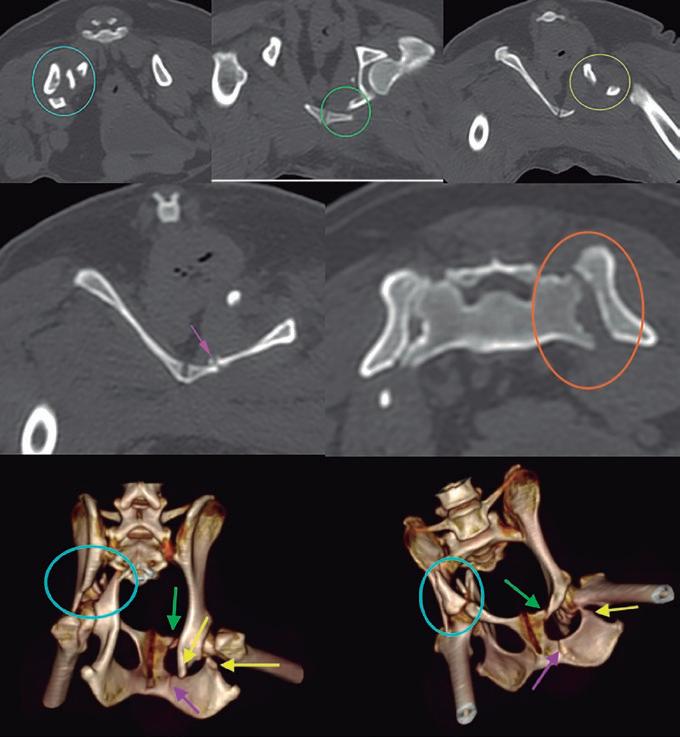

La responsabilidad de los artículos, reportajes, comunicados, etc. recae exclusivamente sobre sus autores. El editor sólo se responsabiliza de sus artículos o editoriales. La ciencia veterinaria está sometida a constantes cambios. Así pues es responsabilidad ineludible del veterinario clínico, basándose en su experiencia profesional, el correcto diagnóstico de los problemas y su tratamiento. Ni el editor, ni los autores asumen responsabilidad alguna por los daños y perjuicios, que pudieran generarse, cualquiera que sea su naturaleza, como consecuencia del uso de los datos e información contenidos en esta revista. De acuerdo con la normativa vigente en materia de protección de datos Grupo Asís Biomedia, SL., es responsable del tratamiento de sus datos personales con la finalidad de enviarle comunicaciones postales de nuestras revistas especializadas, así como otras comunicaciones comerciales o informativas relativas a nuestras actividades, publicaciones y servicios, o de terceros que puedan resultar de su interés en base a su consentimiento. Para ello, Grupo Asís podrá ceder sus datos a terceros proveedores de servicios de mensajería. Podrá revocar su consentimiento, así como ejercer sus derechos de acceso, rectificación, supresión, oposición, limitación y portabilidad enviando un correo electrónico a protecciondatos@grupoasis.com, o una comunicación escrita a Grupo Asís en Centro Empresarial El Trovador, planta 8, oficina I, Plaza Antonio Beltrán Martínez 1, 50002, Zaragoza (España), aportando fotocopia de su DNI o documento identificativo sustitutorio e identificándose como suscriptor de la revista. Asimismo, si considera que sus datos han sido tratados de forma inadecuada,